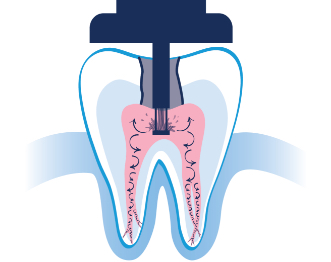

The minimally invasive1 approach of the GentleWave Procedure minimizes manual instrumentation1,3 and instead utilizes a powerful vortex of procedure fluids3 and acoustic energy that cleans the deepest, most complex portions of the root canal system.1,3